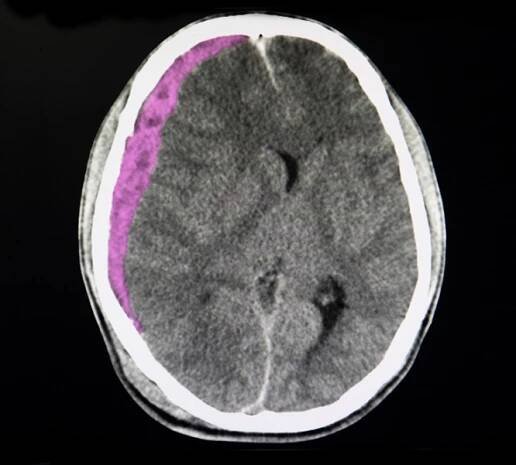

CT sken mozku pacienta po dopravní nehodě s akutním subdurálním hematomem

Michael Schumacher má několik otoků na mozku, jeden se v úterý podařilo lékařům odstranit. Co je subdurální hematom? Druh traumatického poranění mozku, při kterém se přetrhají žilky v ochranné membráně mozku a  dojde k otoku. Krev se hromadí mezi tvrdou plenou mozkovou a povrchem mozku a způsobuje tlak na mozkovou tkáň. Mezi symptomy patří bolest hlavy, zvracení, poruchy vědomí a někdy i zhoršení intelektu.